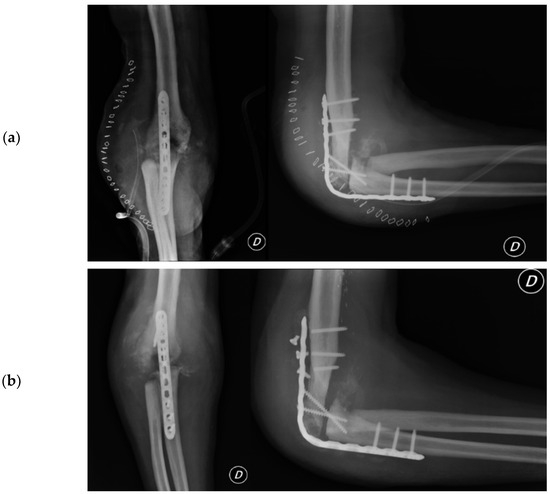

2.4.5. Total Elbow Arthroplasty

2.4.6. Revision Total Elbow Arthroplasty